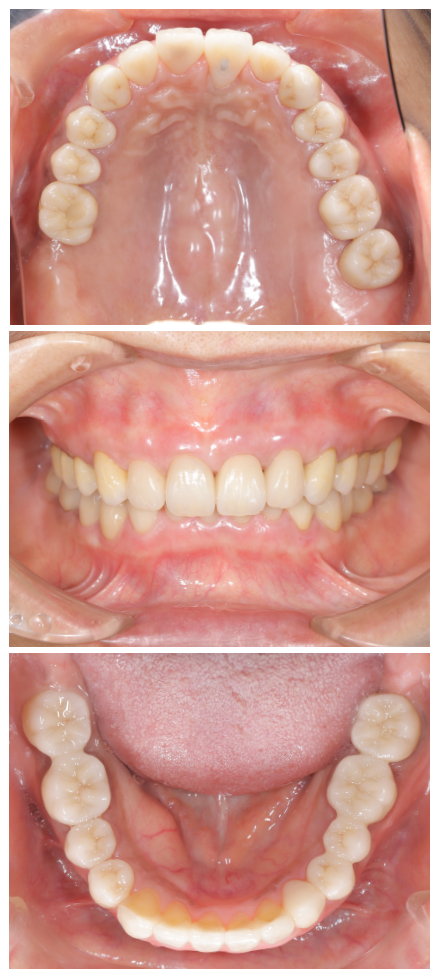

治療完了後の口腔内写真

まずは、患者様の「現状の把握」から始めます。資料収集を正確に行うことにより、正確な診断が可能となり、現状の状態になっている原因を知ることができます。資料収集は歯だけではなく、多角的に顔貌から口元も含めトータル的に行います。

尚、こちらに掲載している写真や画像等は、それら資料収集の内容の1部です。皆様に視覚的にご理解頂きやすい資料のみ掲載しております。